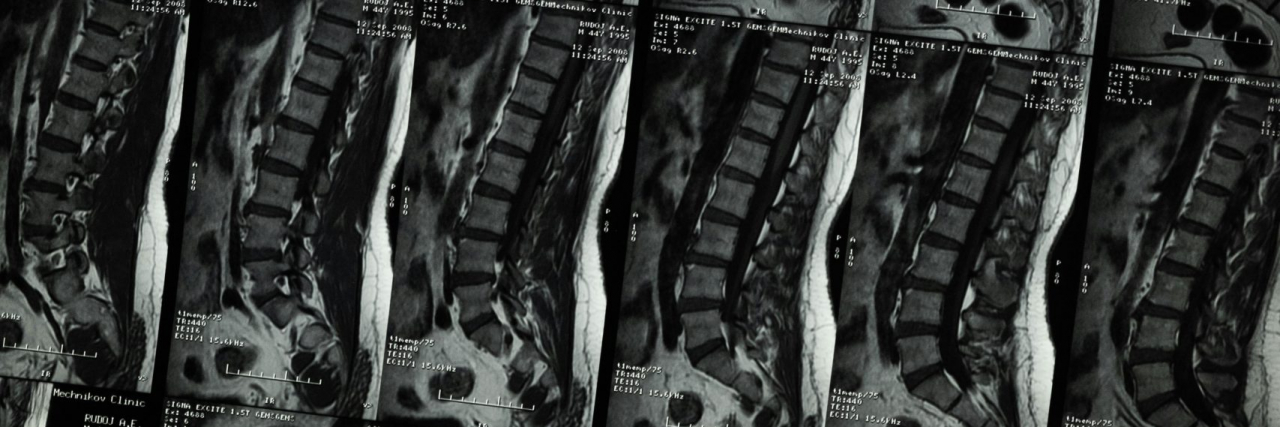

Hi guys I’m new to this app but I struggle with bad anxiety, depression, Ibsd, and kyphoscoliosis I’ve gotten bullied my whole life for it and I don’t have any friends to talk about it with or just to ya know have a friend I was wondering if any of you wanted to be my friend? My undercover name is Maggie and I’m 19 😊 #IBS #Depression #Anxiety #Friends #kyphosis #Scoliosis #kyphoscoliosis